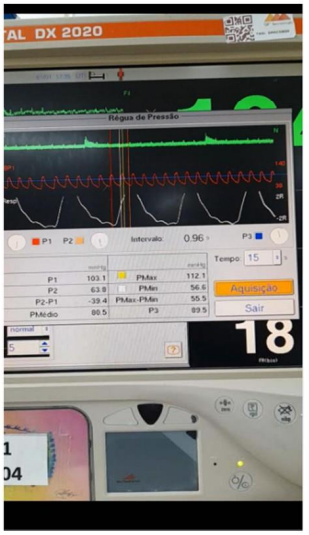

Considere que a imagem apresentada refere-se a um paciente de 40 anos de idade, que se encontra na UTI em VM, com parâmetros ideais para mensuração do delta PP ajustados para VC = 8ml/kg (paciente curarizado). No caso, o monitor multiparamétrico mostra as medidas realizadas.

Considere que a imagem apresentada refere-se a um paciente de 40 anos de idade, que se encontra na UTI em VM, com parâmetros ideais para mensuração do delta PP ajustados para VC = 8ml/kg (paciente curarizado). No caso, o monitor multiparamétrico mostra as medidas realizadas.

Considere que a imagem apresentada refere-se a um paciente de 40 anos de idade, que se encontra na UTI em VM, com parâmetros ideais para mensuração do delta PP ajustados para VC = 8ml/kg (paciente curarizado). No caso, o monitor multiparamétrico mostra as medidas realizadas.